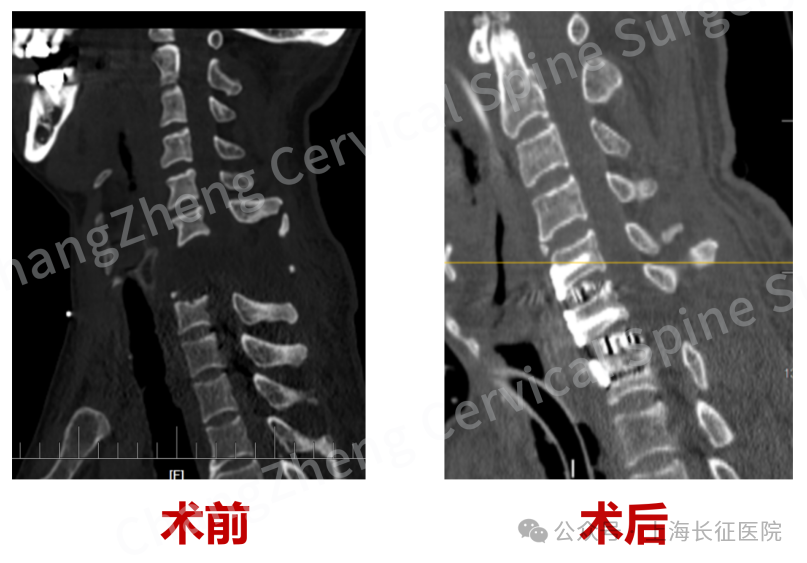

术前、术后影像对比,手术效果良好

眼前这位患者,几乎已被宣判“死刑”。影像学检查显示,患者发生了罕见的大跨度颈椎离断式脱位,脊髓严重挫伤、关键的神经血管结构撕裂。

当时,患者因颈部遭受机械臂重击,导致颈椎瞬间遭受毁灭性损伤,当场高位截瘫、心跳骤停,经紧急心肺复苏才勉强恢复微弱生命体征。影像学检查结果令人震惊:颈椎发生极其罕见的大跨度脱位,其严重程度犹如“身首离断”,已造成脊髓严重挫伤、关键神经血管结构撕裂。